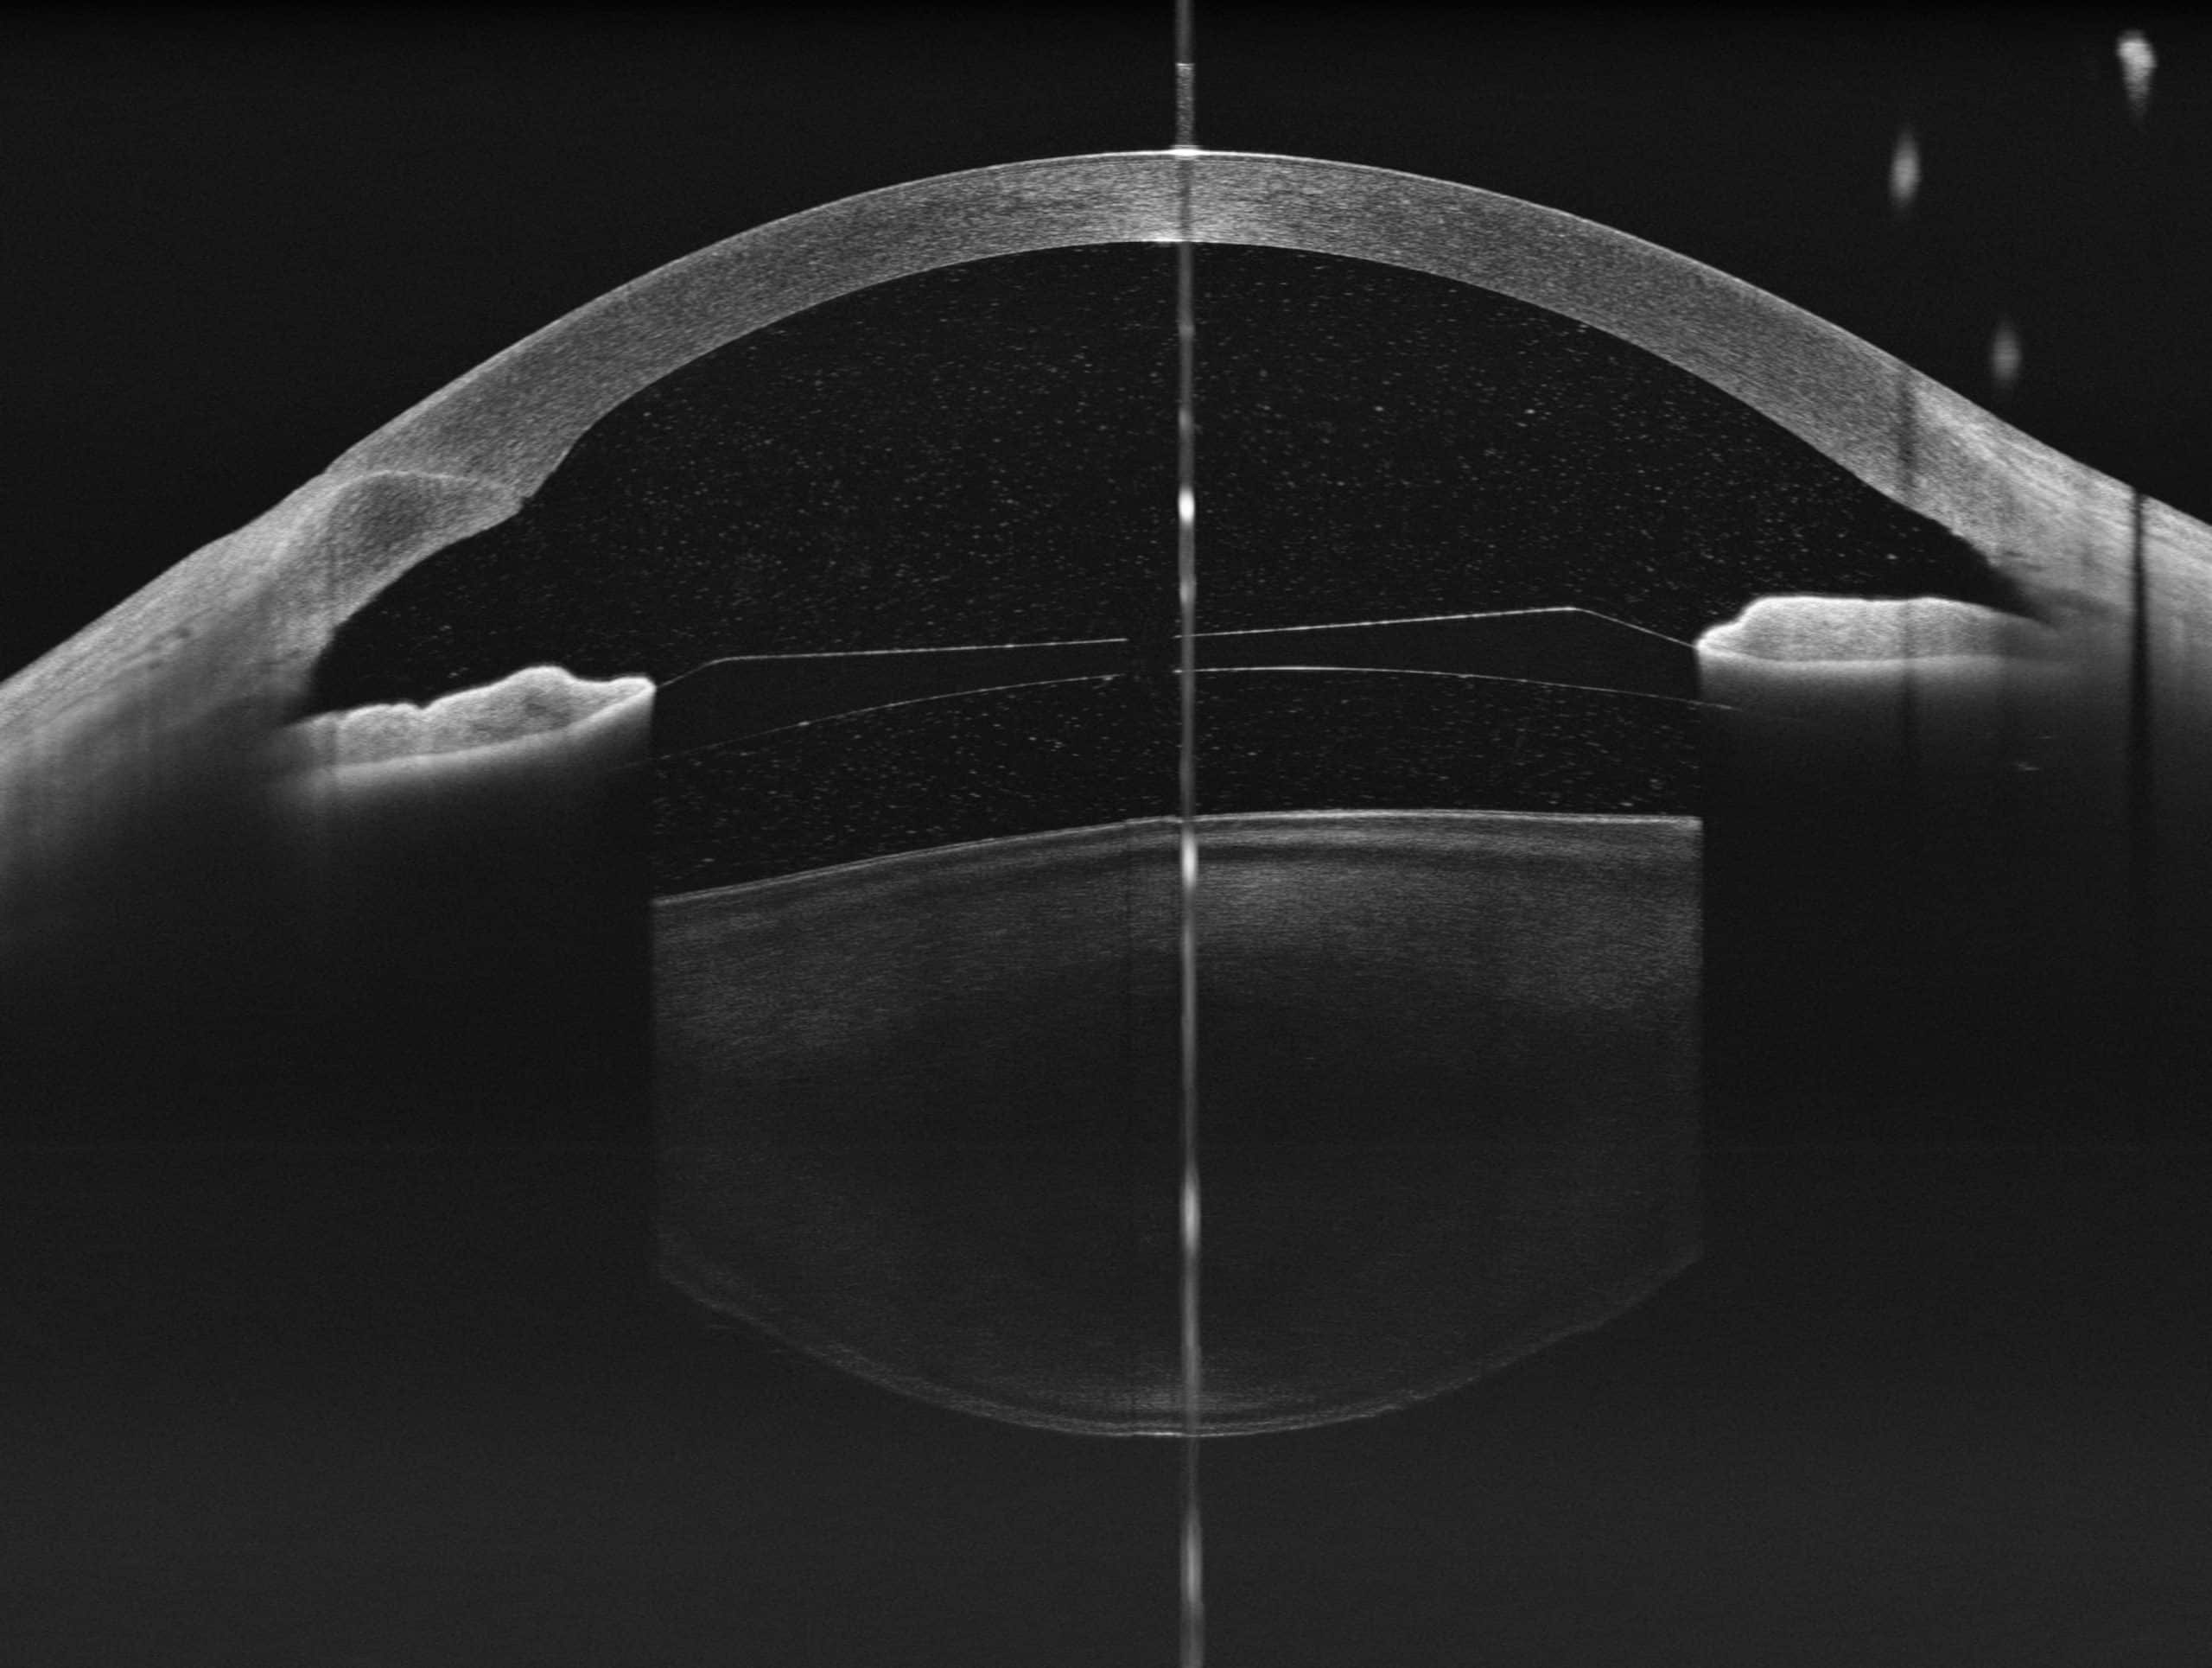

100kHz speed full-range swept-source OCT for anterior and posterior

- HD Anterior Scan with Anterior OCTA

- 15mm Scan depth anterior